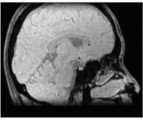

图12A至图41C是根据本发明的一些实施例的患者大脑的示例性检测结果。所述检测结果是基于具有与本发明公开的MR脉冲序列1000相似配置的MR脉冲序列和此处描述的示例性方法生成的。12A-41C are exemplary examination results of a patient's brain according to some embodiments of the present invention. The detection results are generated based on an MR pulse sequence having a configuration similar to the

图12A到图17C是大脑的基本图像。图12A至图12C分别是大脑冠状面、矢状面和横切面的T1加权图像。图13A至图13C分别是大脑冠状面、矢状面和横切面的局部放电加权图像。图14A至图14C分别是大脑冠状面、矢状面和横切面的T2*加权图像。图15A至图15C分别是大脑冠状面、矢状面和横切面的相位图像。图16A至图16C分别是大脑冠状面、矢状面和横切面的相位对比MRA图像,其中图16A至图16C中的相位对比MRA图像是采用包括正FE模块的MR脉冲序列产生的。图17A至图17C分别是大脑冠状面、矢状面和横切面的相位对比MRA图像,其中图17A至图17C中的相位对比MRA图像是采用包括负FE模块的MR脉冲序列生成的。图16A至图17C中的每个图像可以是包括相位信息的相位图像,并且其对应于包括相位信息和幅度信息的复合图像。Figures 12A to 17C are basic images of the brain. 12A to 12C are T1-weighted images of the brain in coronal, sagittal and transverse planes, respectively. Figures 13A to 13C are partial discharge weighted images of the brain in coronal, sagittal and transverse planes, respectively. Figures 14A-14C are T2*-weighted images of the brain in coronal, sagittal and transverse planes, respectively. Figures 15A to 15C are phase images of the brain in coronal, sagittal and transverse planes, respectively. Figures 16A to 16C are phase contrast MRA images of the brain in coronal, sagittal and transverse planes, respectively, wherein the phase contrast MRA images in Figures 16A to 16C were generated using an MR pulse sequence including a positive FE module. Figures 17A to 17C are phase-contrast MRA images of the brain in the coronal, sagittal and transverse planes, respectively, wherein the phase-contrast MRA images in Figures 17A to 17C were generated using an MR pulse sequence including a negative FE module. Each image in FIGS. 16A to 17C may be a phase image including phase information, and it corresponds to a composite image including phase information and magnitude information.